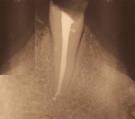

Evidentemente el punto más importante, que determina el tipo de restauración a realizar es la cantidad y distribución de tejido dental sano que se conserva después del tratamiento. En el 90 por ciento de los casos, lo que motiva tener que realizar un tratamiento endodóntico, es la presencia de una caries de ciertas dimensiones en alguna parte de la corona denta y que ha afectado al tejido pulparl. Por otra parte la cavidad del acceso a los conductos radiculares para realizar la endodoncia debe siempre hacerse de una manera concreta, garantizando la vía más recta a dichos conductos.Todo esto hace que la cantidad de tejido dental remanente pueda disminuir considerablemente.

Dependiendo de la situación, el tipo de restauración más adecuada puede ir desde la simple obturación de la cavidad de acceso a la endodoncia, hasta el uso de pernos radiculares o diferentes tipos de recubrimientos para la corona del diente.

Por estos motivos en ocasiones es necesario recubrir el diente completamente para protegerlo al máximo. También, si la cantidad de tejido dentario es muy limitada, puede ser necesario el uso de refuerzos radiculares denominados pernos o postes.